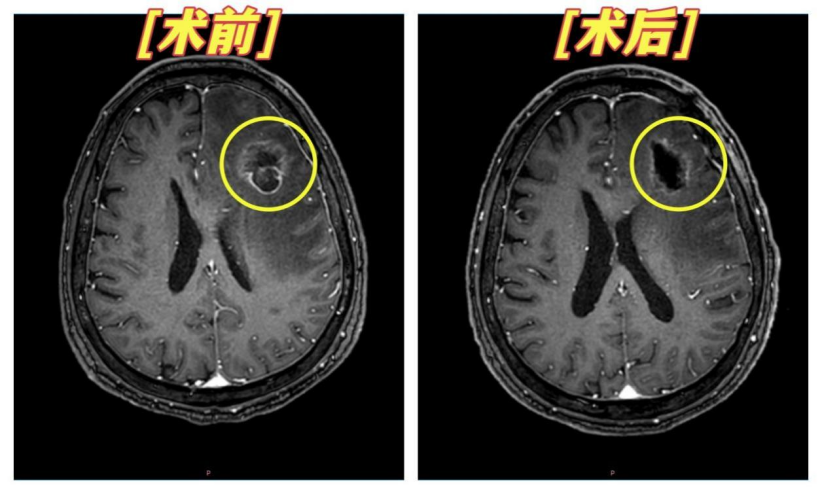

2025年12月,谢先生在常规复查途中突发癫痫、意识丧失,苏醒后右侧肢体无力、言语困难,这正是脑转移病灶进展的典型急症表现。增强磁共振检查结果更揭示了一个少见的医学难题:其右侧额叶转移瘤经放疗后明显缩小,左侧病灶却持续增大并引发严重脑水肿,造成脑组织受压移位。“同一患者、同一治疗,双侧病灶反应却完全相反,这是肿瘤病理异质性的典型信号,意味着两侧病灶的细胞类型或生物学行为大概率存在本质差异。”重庆海吉亚医院神经外科主任童建国分析道,这也是不少晚期肿瘤患者“同药不同效”的核心痛点。

针对左侧持续增大且压迫脑组织的肿瘤,医院紧急启动MDT会诊,神经外科、肿瘤科、影像科等多领域专家协同研判。对脑转移患者而言,病灶与颅内神经、血管的毗邻关系直接决定手术风险与预后,医疗团队借助先进影像技术,术前便精准勾勒出肿瘤的立体位置边界,定制了微创且高精准度的肿瘤切除方案,同时提前规划术后康复路径,最大程度降低手术对神经功能的损伤。

术后病理结果解开了“冰火两重天”的治疗谜团:谢先生左侧肿瘤为大细胞神经内分泌癌,与右侧病灶病理类型存在显著差异,这正是其对放疗不敏感、持续进展的根本原因,而其右肺原发病灶实为非小细胞癌(倾向鳞癌合并大细胞神经内分泌癌)。这一精准诊断为后续全身治疗指明了方向。